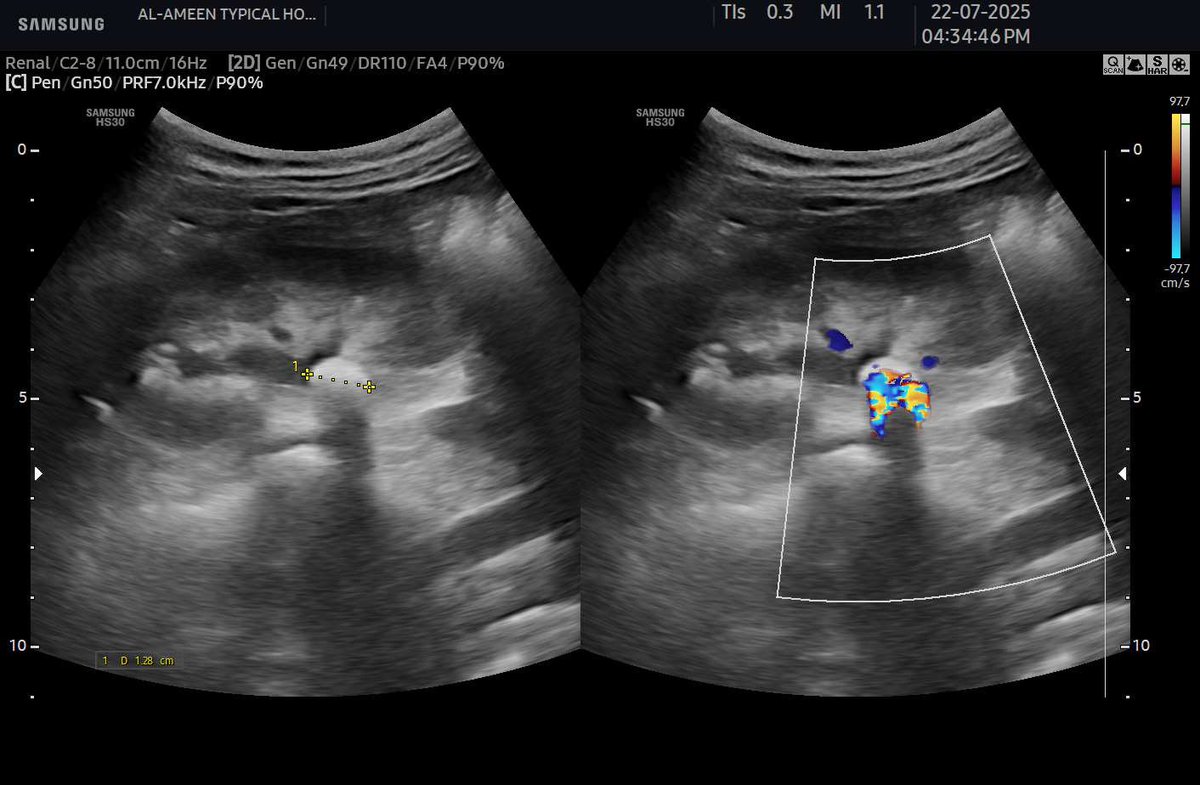

When you Increase the PRF 📈 and Decrease the B mode Gain 📉 You will detect even small calcified stones by the Twinkle artifact. #EchoTech #POCUS

When you Increase the PRF 📈 and Decrease the B mode Gain 📉 You will detect even small calcified stones by the Twinkle artifact. #EchoTech #POCUS